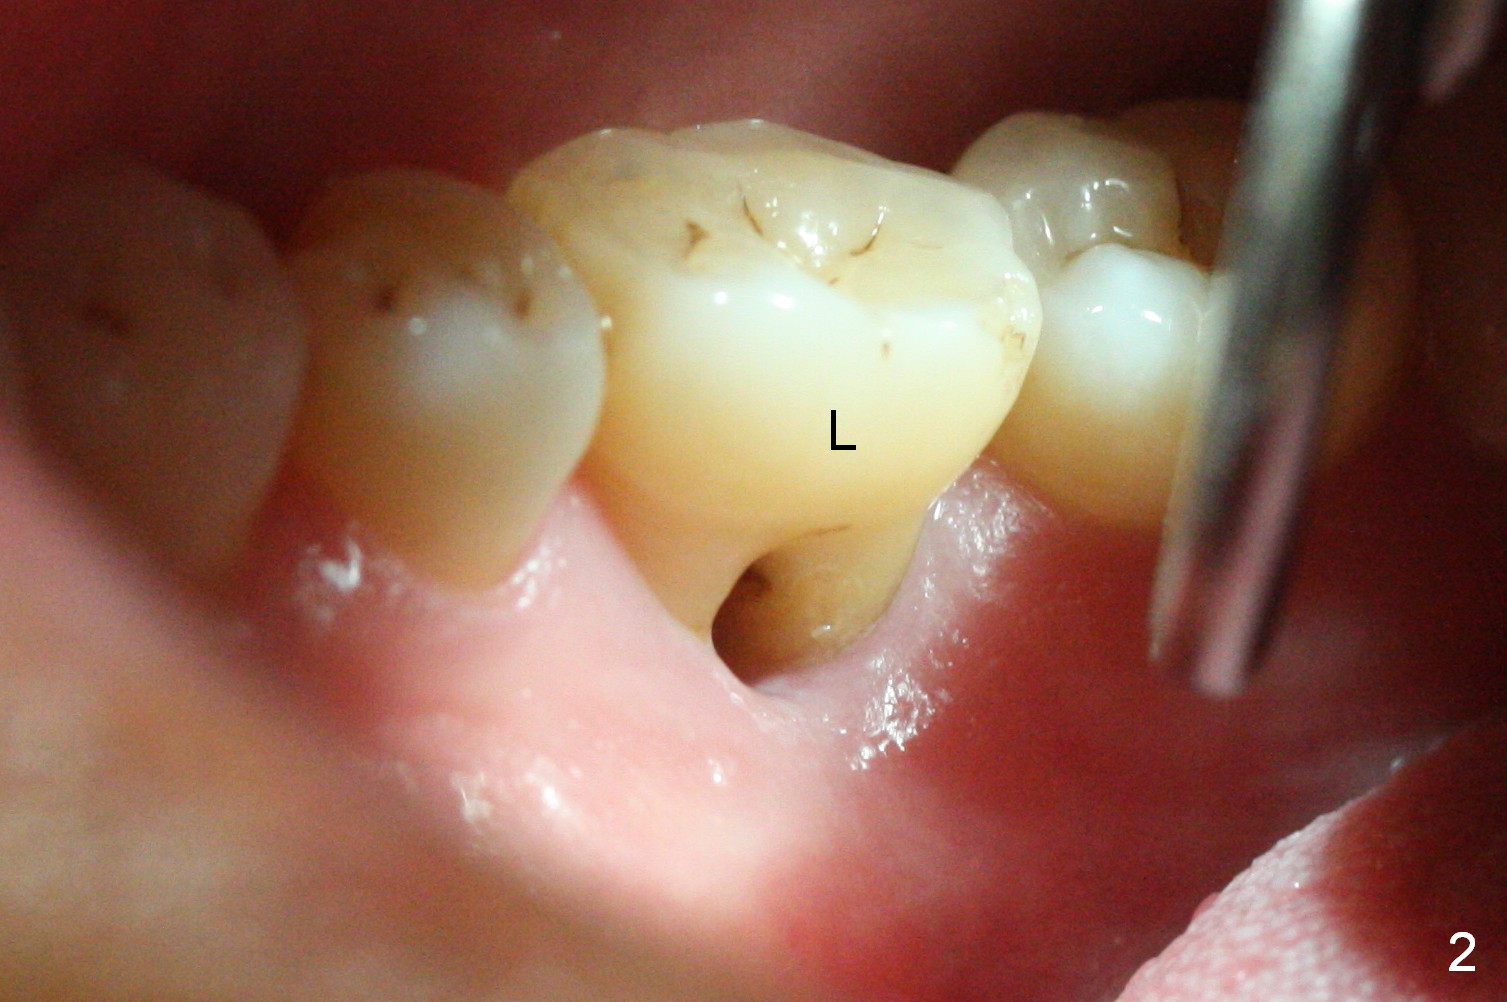

After extraction of the tooth #30 with Class V furcation involvement (Fig.1 (>),2 (L: lingual)), initial osteotomy depth is 8 mm with infiltration anesthesia, but a parallel pin is able to be inserted for 16 mm without pain (Fig.3). There is oozing from the osteotomy. Osteotomy increases in diameter with depth at 8 mm (Fig.4 (3.8 mm drill),5 (5.3 mm tap)). As the Inferior Alveolar Canal (IAC) is indistinct with increased pain during osteotomy, a 5.9x6 mm implant is placed with >50 Ncm following Septocaine infiltration (Fig.6). When bone graft (Fig.7 *) and 7.8x5.5(6) mm abutment (Fig.7,8) are placed, panoramic X-ray is taken (Fig.9). There appears to be a thick layer of spongy bone in the posterior mandible between the red and yellow dashed lines (Fig.5,9). Panoramic X-ray and/or CBCT should be taken if preop PA does not reveal IAC. This patient seems to be a bruxer. There are mandibular tori. Bone loss (furcation involvement) is not proportional to his oral hygiene status. Functional loading (progressive) should be delayed due to bruxism and the short implant.